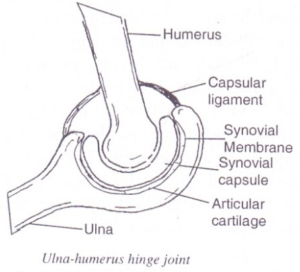

Hinge Joint

Has the basic structure of a synovial joint.

It allows movement in one plane only .i.e. through 1800

The maximum stretch of the limb at this joint is 1800.